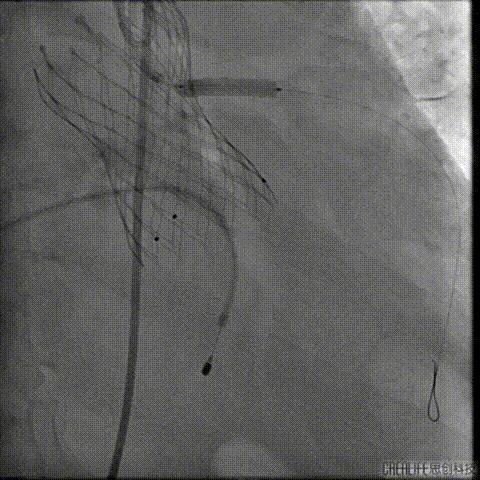

行急诊手术 腹主动脉及左侧股动脉造影

左侧股动脉见造影剂外渗

球囊压迫后植入覆膜支架

复查造影